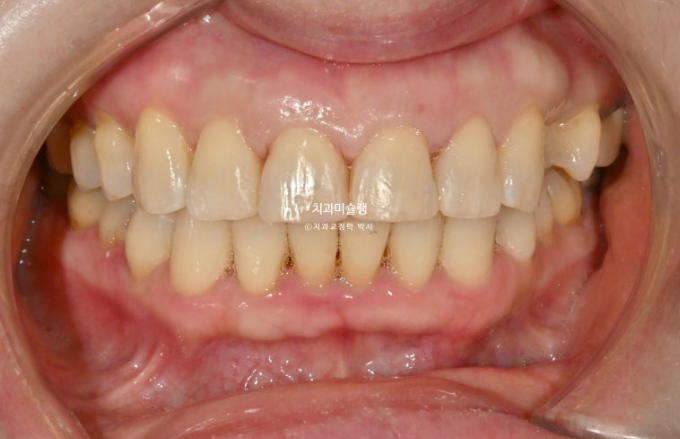

교합은 좋습니다.

이제 전후 비교해보겠습니다.

24.07~26.01

앞니 각도의 개선이 눈에 띕니다.

아래 앞니는 치간삭제와 함입으로 위 앞니 사이사이 벌어진 공간을 이용하여 뻗친 각도와 골출을 개선하였으며

위 아래 앞니 각각 1.5-2mm 가량 뒤로 들어갔습니다.

일년 반에 걸친 치료기간동안 치근흡수는 없고 치근평행도는 좋습니다.

1년 반 치료기간동안 뻗쳐있던 위 아래 앞니 각도가 개선이 되니 입술도 좀 더 편하게 다물립니다.